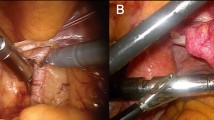

Before every procedure, the medical grade DROP-IN β probe was sterilized with a standard gas-plasma sterilization cycle. During the surgical procedures, it was used through a standard 12-mm assistant trocar (see Fig. 3). Pick-up of the DROP-IN β probe was simple using the standard da Vinci tools (e.g., ProGrasp Forceps instrument). The surgeon was able to use the probe to scan the field autonomously exploiting all 6 available degrees of freedom, without the need of any help from the assistant. In each patient, the DROP-IN probe was used to perform lymph node examination for around 20 min in total, having therefore reduced impact on surgery duration. No complications related to the use of the prototype probe nor of the [68Ga]Ga-PSMA tracer were observed, and no issues were encountered in the sterilization procedure.

A Operating room during one of the procedures: the black cable coming from the drop-in probe can be distinguished. B MIP image of 68 Ga-PSMA-PET of one of the considered patients (Pt. #3). C View of the da Vinci monitor as seen by the surgeon during the procedure (Pt. #5), including the TilePro split-screen option to view the probe measurements directly in the surgical console

A Example of data acquired when scanning a given district with the best discrimination algorithm. Blue data represent counts considered to evaluate the background, while orange and green ones represent measurements performed on tumor and healthy tissue respectively, according to pathology examination. The label reports the name and pathology code of the considered sample, while the color of its surrounding border represents whether the sample was identified as probe-positive (red) or probe-negative (green) by the algorithm. B, C Screenshots of the DROP-IN probe performing measurements on samples M and N respectively